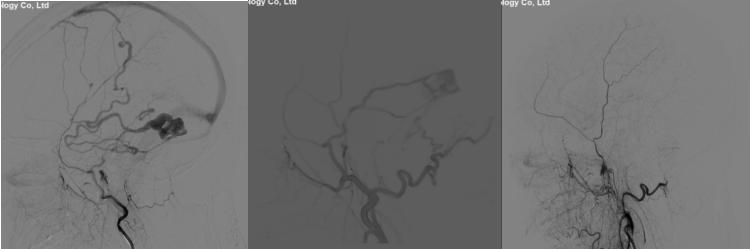

术前检查完成后,神经外科介入团队于6月14日在局麻下给患者行全脑血管造影检查提示“颅内多发动脉粥样硬化伴狭窄,左侧大脑中动脉M1段重度狭窄”。左侧大脑中动脉仅余一线,狭窄率接近99%。考虑患者反复出现脑梗死与左侧大脑中动脉狭窄有关。且其它血管对左侧大脑中动脉供血区域基本无代偿,一旦发生大脑中动脉闭塞将发生严重后果,有明确的手术指征。与患者及家属沟通病情后决定行颅内动脉狭窄血管内介入治疗。后改为气管插管全身麻醉,术中严格控制血压。因患者血管迂曲,神经外科介入团队使用多种技术手段最终成功到达狭窄部位。行左侧大脑中动脉狭窄球囊成形术后,观察30分钟后仍有残余狭窄,给于置入颅内动脉支架一枚。复查血管造影提示狭窄血管完美修复。

术前造影提示左侧大脑中动脉重度狭窄,术后血管完美修复